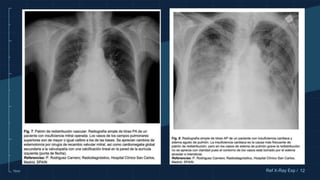

PATRÓN DE REDISTRIBUCIÓN

VASCULAR

Consiste en una inversión de la relación

normal entre los vasos apicales y basales,

es decir, los vasos de los ápices son

mayores o iguales que los de las bases

pulmonares. (Congestión venosa pulmonar

ocasionada o acompañada por sobrecarga y

fallo de las cavidades cardiacas izquierdas)

Cuando identifiquemos un patrón de redistribución vascular debemos hacer un diagnóstico

diferencial de causas que provoquen hipertensión venosa pulmonar